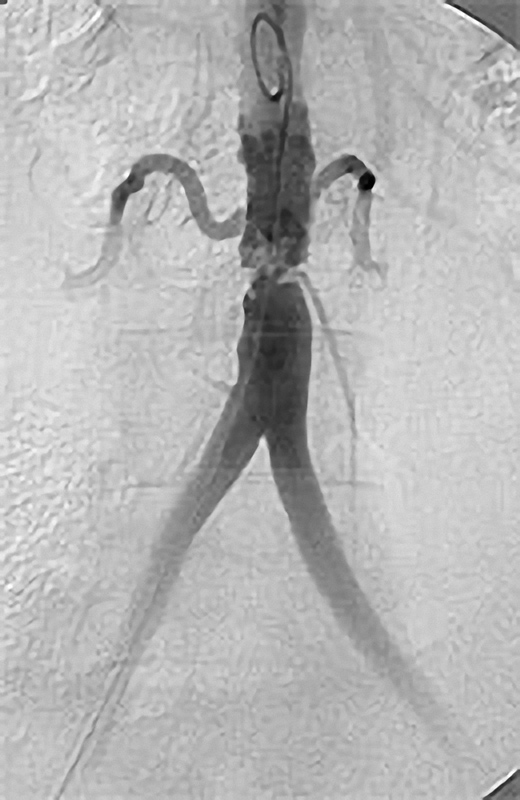

Grundprinzip der Kathetertherapie ist die Gefäßbehandlung über einen millimetergroßen Hautschnitt unter örtlicher Betäubung und das Vorschieben von Plastikschläuchen (Kathetern) in die Gefäße. Über diesen Zugang (meist in der Leisten- oder Ellenbeuge) können Gefäßeinengungen aufgeweitet oder auch Gefäßverschlüsse wiedereröffnet werden (Ballon- oder Stentverfahren). Diese Verfahren werden immer weiter entwickelt und so sind nun auch Behandlungen des Bauchaortenaneurysmatas oder das Einbringen einer Herzklappe auf diesem Wege möglich.

Möglichkeiten der Perkutanen Transluminalen Angioplastie (PTA)

Die PTA (Perkutane Transluminale Angioplastie) im Beckenbereich ist ein minimalinvasives Verfahren zur Behandlung von verengten Beckenarterien. Dabei wird ein dünner Katheter mit einem Ballon über die Leiste in die verengte Arterie eingeführt. Der Ballon wird an der Engstelle entfaltet und dehnt die Arterie auf, um den Blutfluss zu verbessern. Oft wird zusätzlich ein Stent eingesetzt, um die Arterie dauerhaft offen zu halten. Die PTA wird meist in örtlicher Betäubung durchgeführt und ermöglicht eine schnelle Erholung. Sie ist eine bewährte Alternative zur offenen Operation bei Durchblutungsstörungen im Becken- und Beinbereich.